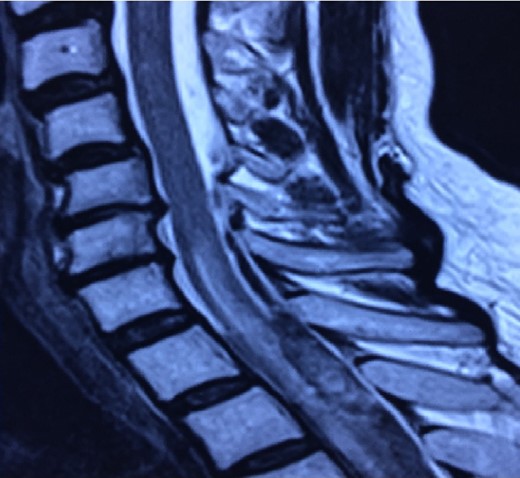

Patient presented sudden onset with dorsal pain followed immediately by bilateral lower extremity paresis that progressed to complete paraplegia with bowel and bladder dysfunction over 15 min. The patient was taken to a local hospital where an MRI was performed that demonstrated a SSDH extending from T4 to T7 with some intramedullary enhancement noted (Figs 1 and 2). Loss of sensory level from T10 up to ~T8 level. She denied upper extremity complaints.

When the subdural hematoma is discovered during the hyperacute phase, such as with the patient described in the case report, the blood collection is visualized as isointense and hyperintense in T1 and T2 signals, respectively. The intensity will normally vary according to the phase in which the MRI has been performed [4, 7, 8]. Once the presence and location of the subdural hemorrhage are determined it is fundamental to decide the optimal treatment for the patient unhesitantly.